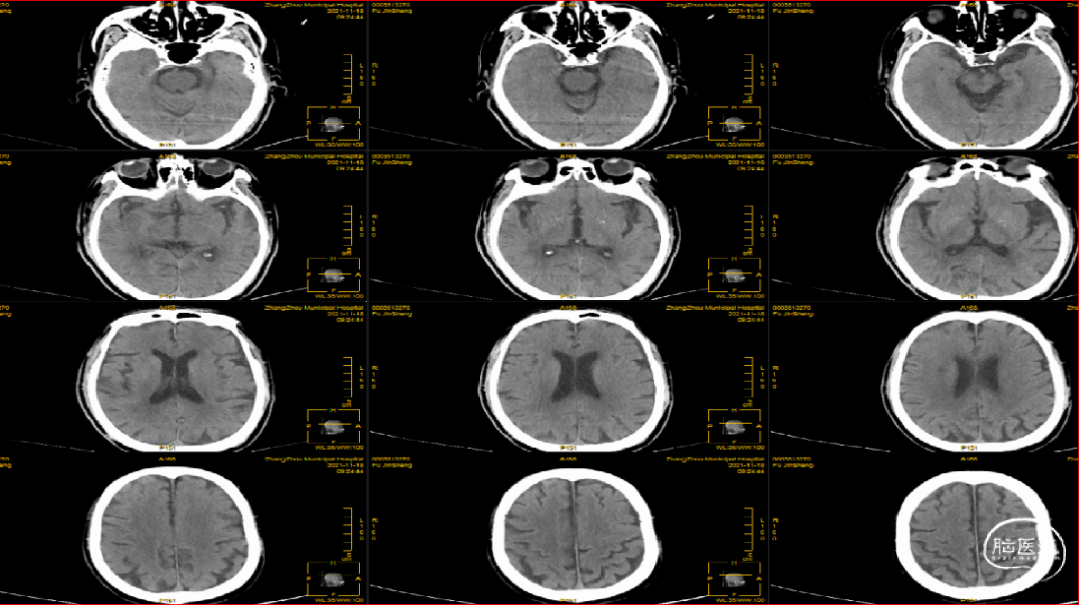

术前影像学检查结果

急性右侧脑梗死,右侧大脑中动脉闭塞,心房颤动,高血压,心功能不全。

术前CTA可知责任血管为右侧大脑中动脉,遂在泥鳅导丝及4F多功能管的引导下,直接将8F导引导管送至右侧颈内动脉C1段,造影示右侧大脑中动脉M1远端下干闭塞,同侧大脑前动脉通过脑膜支向大脑中动脉供血区代偿供血,代偿ASTRIN分级2级,将SKATHI远端通路导管送至颈内动脉C4段,随后微导管(Rebar 18)在微导丝(Synchro 14)辅助下,小心通过大脑中动脉下干闭塞段至M2段,再将SKATHI远端通路导管顺利送至大脑中动脉闭塞段近端,并抵住血栓近端,撤出微导丝及微导管,用50ml注射器保持负压吸引抽吸导管,约1分钟后缓慢回撤中间导管至颈内动脉C4段,抽出多枚栓子,复查造影见右侧大脑中动脉各分支完全显影,TICI3级,血流速度正常。